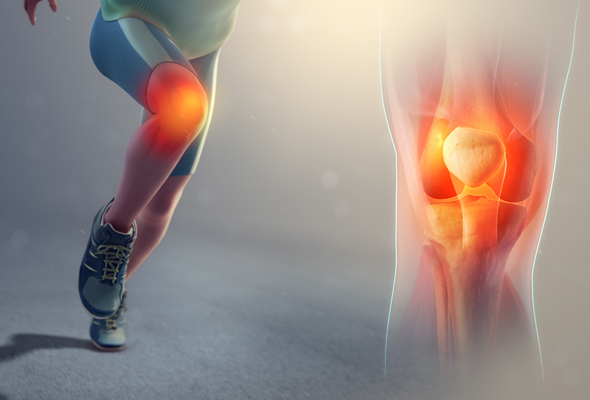

His areas of expertise include fracture and trauma care, providing prompt and effective treatment for bone and joint injuries. Dr. Siddiqui specializes in joint replacement surgeries, including Total Knee Replacement and Total Hip Replacement, helping patients regain mobility and live pain-free lives. He also treats sports and ligament injuries with advanced arthroscopic procedures for faster recovery and minimal discomfort.

Sports and ligament injuries treated with care, therapy, faster recovery.

Minimally invasive arthroscopy treats joint problems, ensuring accurate diagnosis, faster recovery, less pain.